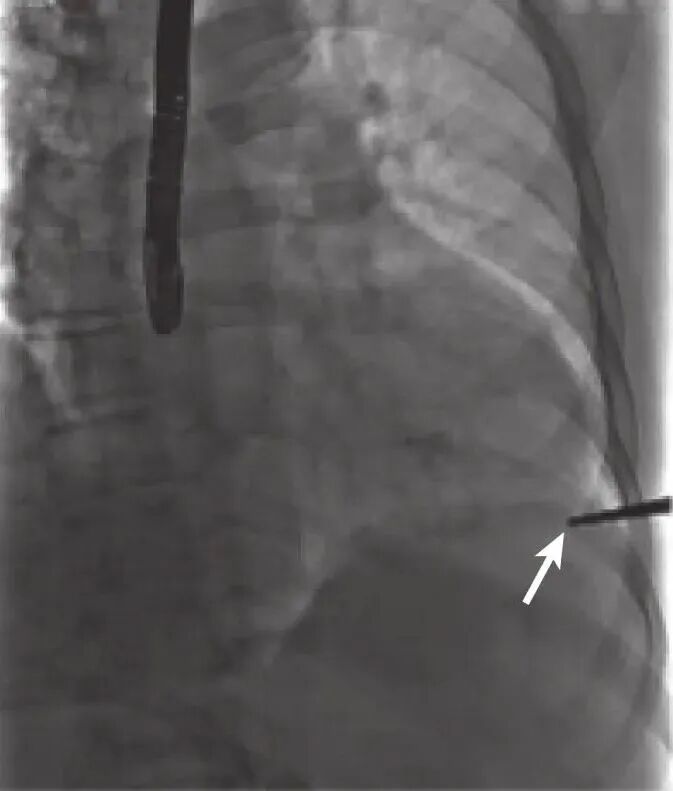

荷包缝合完成后,给予肝素(0.5~1mg/kg)使全血活化凝血时间(activated clotting time,ACT)维持在250~400s。经股动脉鞘送入“猪尾”导管至主动脉瓣环平面,可作为主动脉瓣位置的参照。经心尖荷包正中送入穿刺针,针尖垂直于心肌刺入。心室收缩能见鲜红的氧合血喷出可以初步确定进入左室。如果没有氧合血喷出,表明穿刺针有可能刺入室间隔;若能看到搏动的静脉血,表明穿刺针可能已经穿过室间隔进入右心室,应退出重新穿刺。当确定有鲜红血液喷出时,保留穿刺鞘退出穿刺针,送入导丝尝试跨过主动脉瓣口,过瓣后用TEE反复确认导丝是否缠绕二尖瓣腱索,如果存在缠绕,应撤出导丝,避开缠绕后重新跨瓣(图7)。随后沿导丝送入5F鞘管,通过鞘管送导引导管及交换导丝,两者配合使导引导管进入降主动脉,交换加硬导丝(extra stiff),将加硬导丝头端塑型盘成一小圈,DSA下沿导管将导丝送入髂动脉平面,以避免后续操作过程中导丝进入腹腔重要分支血管导致损伤,经加硬导丝交换成14F或16F鞘管,一方面可扩张穿刺点以利于植入器顺利进入,另一方面可以装载球囊用于预扩和后扩。

图片

图7 跨瓣时避免导丝缠绕二尖瓣腱索

(a:TEE下导丝紧贴室间隔跨过主动脉瓣口;b:TEE下导丝远离室间隔,靠二尖瓣前瓣侧跨过主动脉瓣口;c:DSA下导丝平滑通过主动脉瓣口,a、c:导丝与二尖瓣腱索无缠绕;d:DSA下导丝在心室内稍有打折,b、d:导丝与二尖瓣腱索有缠绕,需重新跨瓣;TEE:经食管超声心动图;DSA:数字减影血管造影)